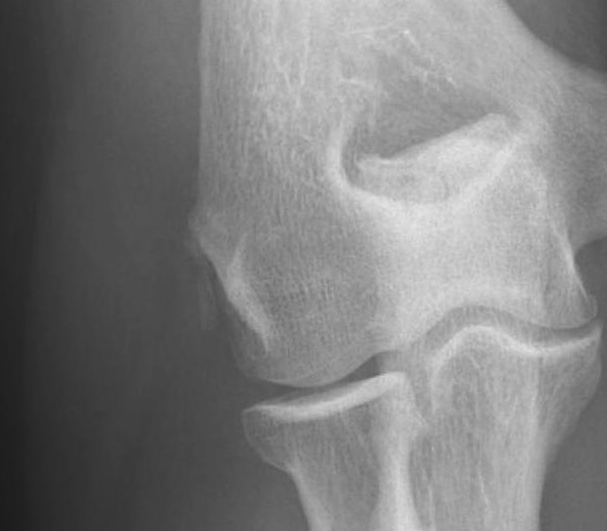

Xray

May see dystrophic calcification